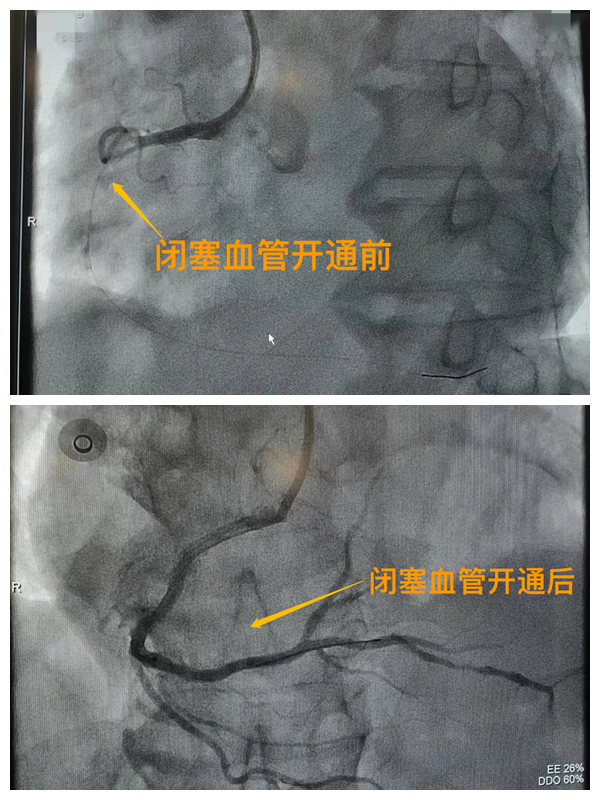

活動開始前,院長王瑾對現(xiàn)場群眾進行了健康科普宣講,她以近期醫(yī)院救治的多例急性心肌梗死患者的癥狀、發(fā)展、急救、手術(shù)、康復(fù)全流程情況為例,向小區(qū)群眾講述了心梗的發(fā)病癥狀和院前急救注意事項,以及要及時通過120送至專業(yè)的胸痛中心開展科學(xué)、規(guī)范的急救手術(shù)的必要性,講述了心梗患者轉(zhuǎn)危為安的全過程,得到了廣大群眾的共鳴與好評。

市二院胸痛中心于2021年12月23日通過中國胸痛中心認證,成為國家級胸痛中心,先后開展了冠心病的介入診療、心律失常的心內(nèi)電生理檢查及射頻消融治療、永久起搏器植入、先天性心臟病的介入封堵及臨時起搏器植入、主動脈內(nèi)球囊反搏治療等,完成心臟介入手術(shù)3000余例。多次創(chuàng)造從入院至行急診介入手術(shù)開通血管(入門-導(dǎo)絲通過)30分鐘以內(nèi)記錄,極大保證了患者的生命安全,提高了預(yù)后質(zhì)量,挽救了眾多急性心?;颊叩纳?。(尹紅婭       張   靜)